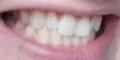

Мне 24 года. С 13-15 лет носила брекеты. В 19 прорезались зубы мудрости, и зубы верхней челюсти стали выступать из зубного ряда. Мучиться с брекетами больше не хочу.

Подскажите, есть ли ещё варианты исправления такой ситуации как у меня, хотя бы эстетически? Может виниры или элайнеры какие?

Конечно нельзя, проблема, действительно, связана с восьмыми зубами, которые необходимо удалить как можно раньше и после обратиться к ортодонту. К сожалению, выпирающий зуб настолько вылез из зубного ряда, что даже обточка и установка коронки в Вашем случае не дадут хороших результатов, да это и неправильно.